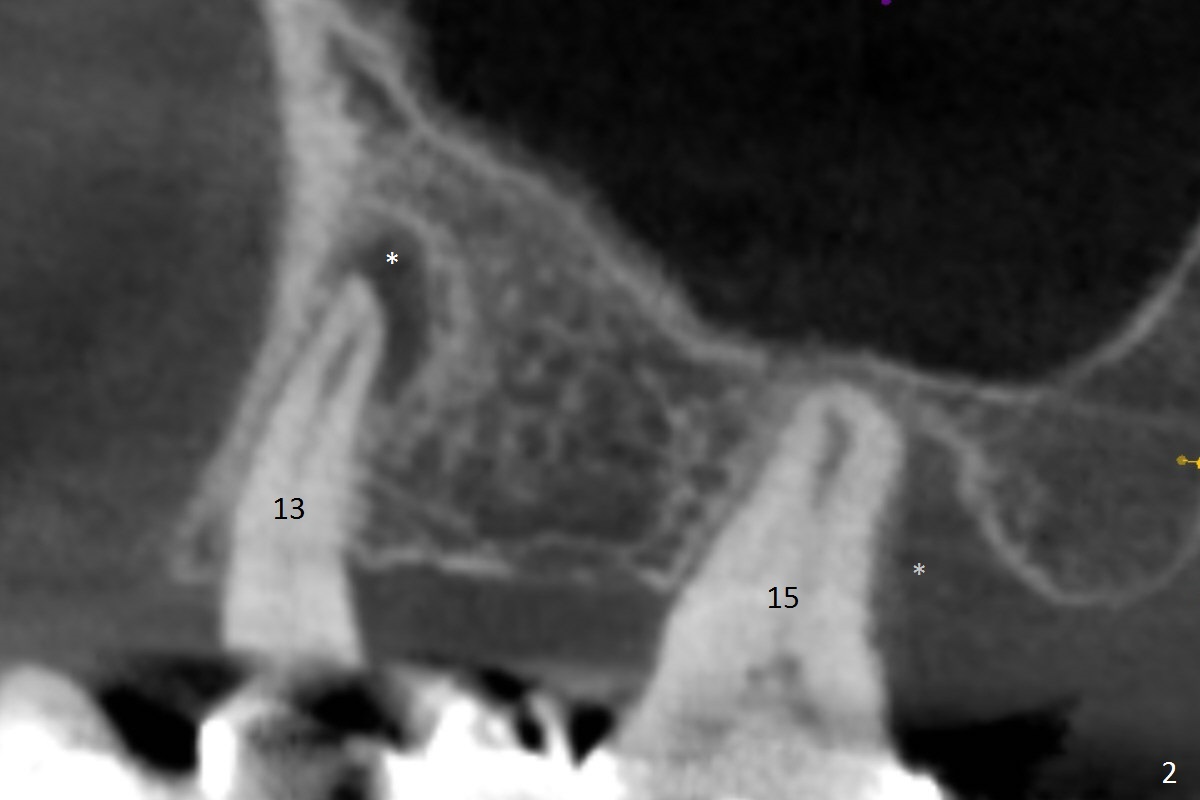

While the 64-year-old woman is undecided on the lower right quadrant treatment, she has had periodic pain and swelling in the upper left quadrant (Fig.1). CBCT sagittal sections show periapical radiolucency at #13 and bone loss distal to #15 palatal root (Fig.2,7). Endodontic treatment is the 1st option to save the long bridge (#9-15, Fig.1).